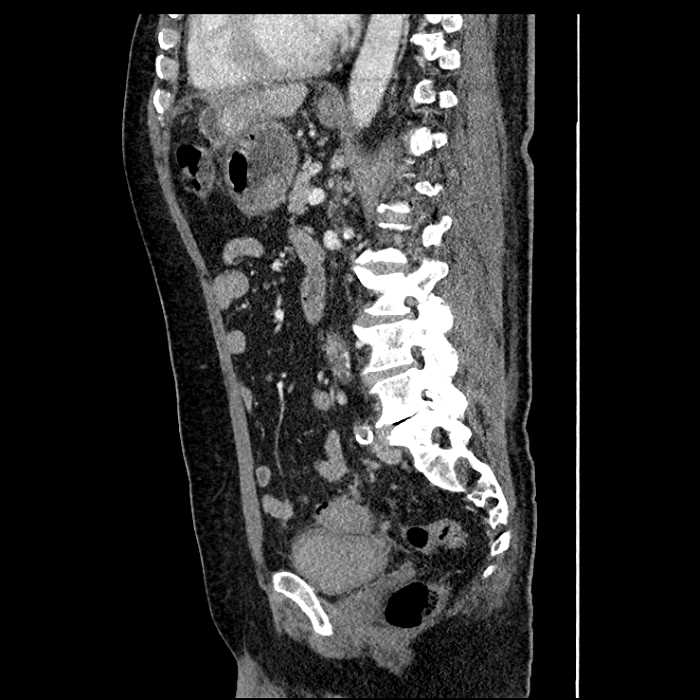

• Mild mural thickening of a segment of the sigmoid colon with adjacent fat stranding and a 1.5 cm fluid and gas collection along the tip of an inflamed diverticulum

• Loss of the normal fat plane between this collection and adjacent loops of small bowel, which demonstrate mural thickening

• No bowel obstruction

Acute sigmoid diverticulitis complicated by a small contained perforation and a large abscess in the right hepatic lobe. Additional small subcapsular abscesses along the anterior margin of the left hepatic lobe.

Additionally, loss of the normal fat plane between the peridiverticular collection and adjacent thickened loops of small bowel raises the potential for an enterocolonic fistula.

Hepatic abscess showing the double target sign with low density internally surrounded by a thin inner enhancing rim (red arrow) and ill-defined outer low density rim (yellow arrow). Blue arrow indicates an internal septation. Red arrows: additional smaller subcapsular abscesses. Red arrow: focal contained perforation associated with diverticulitis.